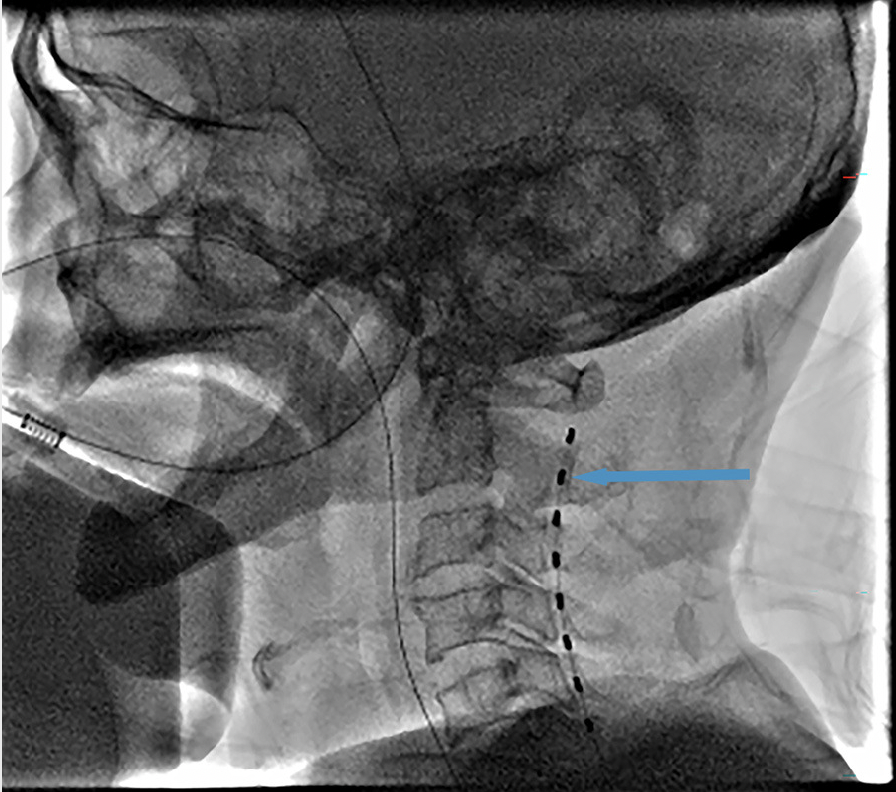

近日,有研究发现通过短期的脊髓电刺激技术可能有效改善因原发性脑干出血致患者昏迷的意识状态。该发现可能为这类患者提供更多的治疗手段,从而改善患者的生活质量。这项研究发表在了《FrontiersinNeurology》上。原发性脑干出血(PBSH)是一种脑出血亚型,大多数情况下发生在脑桥,占脑内出血病例的5%至10%。这种疾病以症状突然发作、神经学快速恶化、预后差和高死亡率(30%-90%)为特征。脑干中的血管异常破裂引起的脑损伤可能导致严重的意识障碍(DOC),通常对术后恢复产生严重影响。因此,开发针对PBSH引起的DOC的有效策略将有助于临床治疗。目前对DOC的治疗仍缺乏一种根本性的策略。近年来已经研发了几种新的非侵入式神经调控治疗方法,包括经颅直流电刺激(tDCS)和重复经颅磁刺激(rTMS)。根据最近的研究,严重脑损伤后意识丧失与神经回路的紊乱密切相关(如皮层-丘脑和皮层-皮层连接)。根据其原理,非侵入式神经调控治疗并不直接调节神经回路,特别是丘脑皮层连接。脊髓刺激(SCS)已成为DOC的一种关键和有效的外科治疗方法,因为其操作相对容易、安全性高、适应范围广、有效性强且能直接调节神经回路。近期,短期脊髓刺激(st-SCS)已被用于DOC的恢复治疗,但尚不清楚它是否对PBSH引起的DOC产生影响。14名患者接受了为期两周的st-SCS治疗。使用昏迷恢复量表修订版(CRS-R)对每位患者的意识状态进行评估。记录了植入SCS治疗前(基线)和14天后的CRS-R评估分数。刺激方法:SCS手术后,脊髓电刺激持续14天。每天从早上8点到晚上8点进行5分钟开/15分钟关的循环。机器的参数设置为:电压2.0V、频率70Hz和脉宽210us。该研究证明了st-SCS在治疗PBSH诱导的意识障碍中的安全性和可行性,并且对于MCS+患者来说,它是最有效的治疗方法。在st-SCS治疗2周后,5例患者脱离MCS状态,超过70%的患者的CRS-R评分有所改善,大约50%(7/14)的患者表现出神经功能改善。St-SCS最初用于缓解疼痛,并已成为早期疼痛患者的不可或缺的治疗手段。近年来,随着更广泛的st-SCS研究,它已被用于意识恢复。该研究尝试对于PBSH的DOC患者进行早期(1.27±0.31月)干预的st-SCS,研究结果取得了一定的疗效。这些结果对于将来在PBSH诱导的意识障碍中应用st-SCS非常有希望。本研究样本量较小,预后评估未采用神经电生理监测,且干预的对象均处于疾病早期阶段,因此,st-SCS在PBSH患者的康复治疗中的作用仍需被进一步证明。内容来源:https://www.ncbi.nlm.nih.gov/pmc/articles/PMC10064090/pdf/fneur-14-1124871.pdf